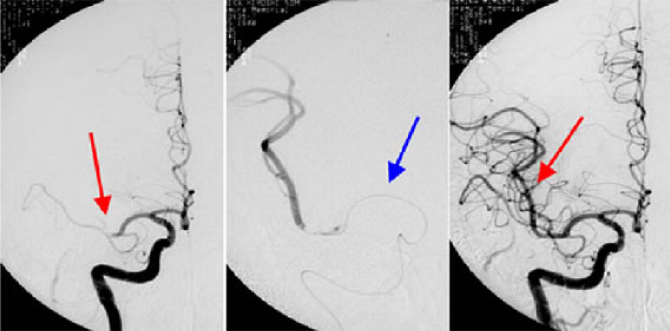

左:赤矢印のところで血管がつまっています(中大脳動脈閉塞)

中:青矢印がマイクロカテーテル。この先から血栓溶解剤を注入

右:再開通が得られています